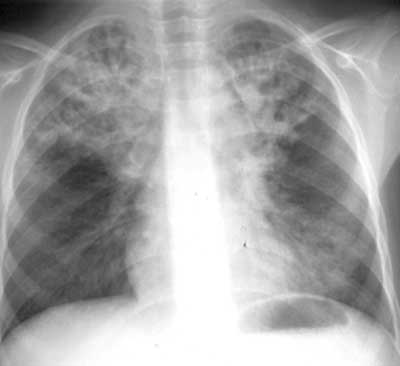

Муковисцидоз.

Рис. 1. Изменения в легких при муковисцидозе.